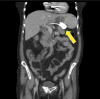

Introduction: Obesity levels mean an increased presentation of patients with Laparoscopic adjustable gastric banding (LAGB). Method: Literature search revealed a paucity of information on ultrasonography to diagnose a slipped LAGB. Conclusion: 2D Ultrasonography with a standard low frequency curvilinear probe proved to be a simple, effective method of diagnosing slipped Laparoscopic adjustable gastric banding (LAGB). We suggest the inclusion of routine abdominal ultrasound (after drinking water to improve sensitivity of the test) as part of the routine workup of suspected LAGB slippage.